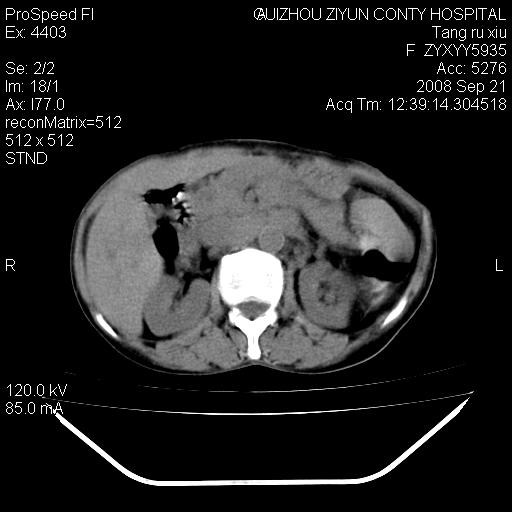

f、57岁,上腹痛.2月,近来胸闷。2月前在外院摄胸片示左侧胸腔少量积液。

(患者腹痛入院,欲吐,临床医生说禁饮,所以没有口服对比剂)

肝脏大小形态尚可,其实质内可见多发大小不等的低密度影,边缘模糊。肝门区结构紊乱,腔静脉腹主动脉旁可见多发软组织密度影,部分融合成团块状,并向下延伸。胰腺及十二指肠结构显示不清。腹腔内脐后肠管走形僵硬,管壁可见增厚。盆腔内可见多个淋巴结影。所扫层面左侧胸腔可见大量弧形水样密度影,其内侧可见被压缩的肺组织影。左侧胸壁可见一小结节样软组织密度影,边缘模糊。心脏纵隔向右侧移位。心脏包膜内可见囊样低密度影,其内侧心房室周围可见一圈气体样密度影。纵隔内大血管旁可见多发软组织团块影,部分融合。

1.腹膜后淋巴瘤侵及肝脏,肺内及纵隔内多发转移。2.左侧大量胸腔积液并压缩性肺不张。3.心包脓肿可能,转移不除外。4.脐后局部肠管管壁增厚,考虑炎症可能,肿瘤不除外。